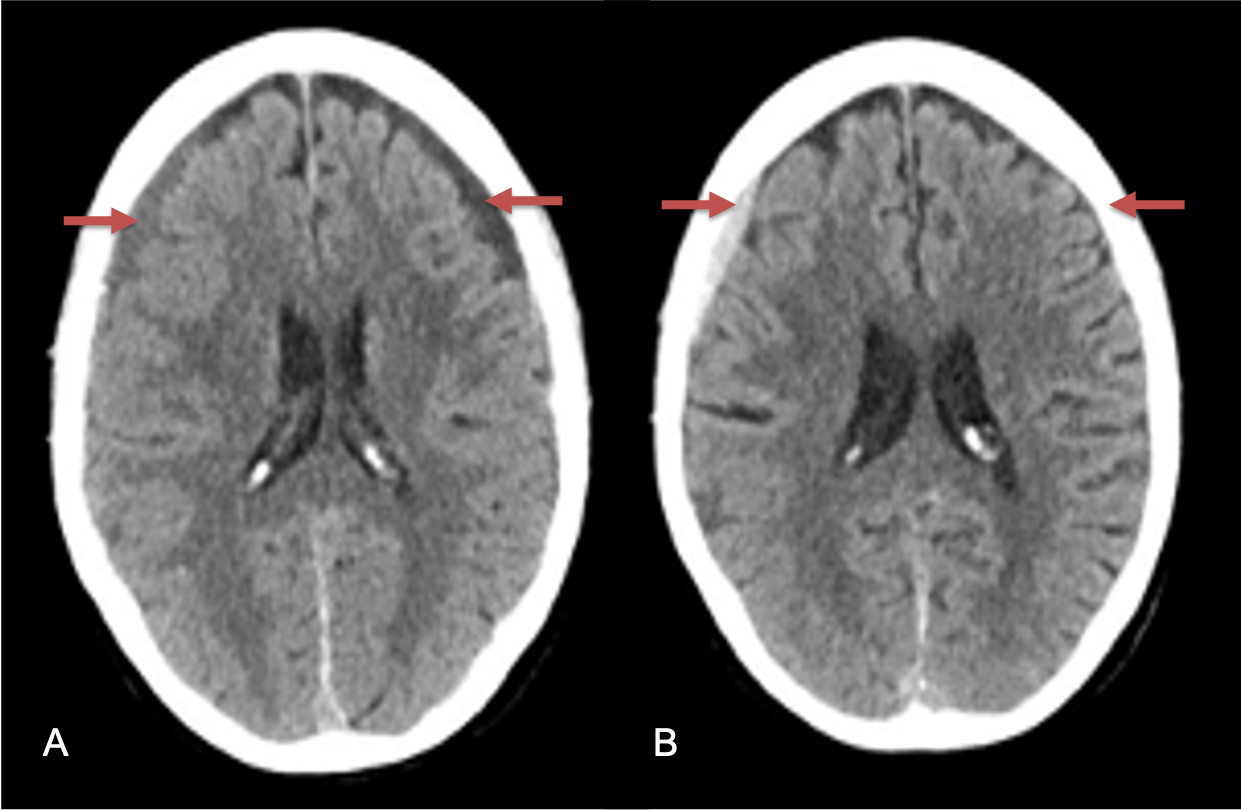

CT follow-up at 1 week demonstrates early resorption. 2 weeks post MMA embolization, resolution of the left subdural collection with new small thin acute hemorrhage in an otherwise stable right subdural collection is observed (Figure 3. A and B).

Figure 3. A) 1 week post MMA embolization demonstrating decreasing thickness bilaterally B) 2 weeks post MMA demonstrates resolution on left, with small new acute component on right with overall decreased thickness.